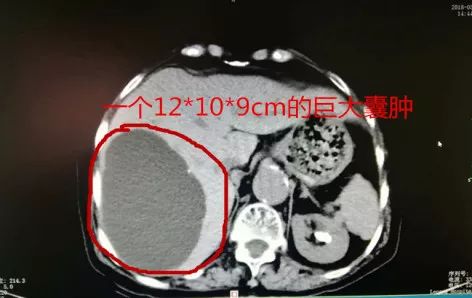

经过CT诊断,

刘奶奶体内居然有一个

12*10*9cm的肝囊肿!